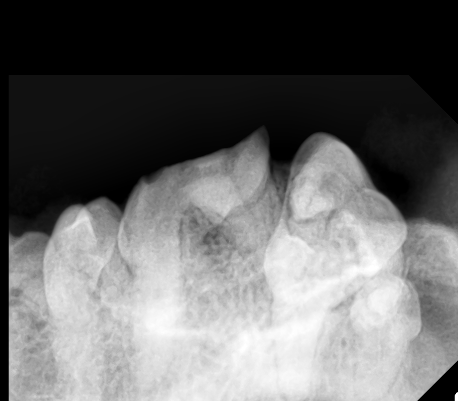

歯科レントゲンではこのようになっており、歯髄が露出しているのが分かります。